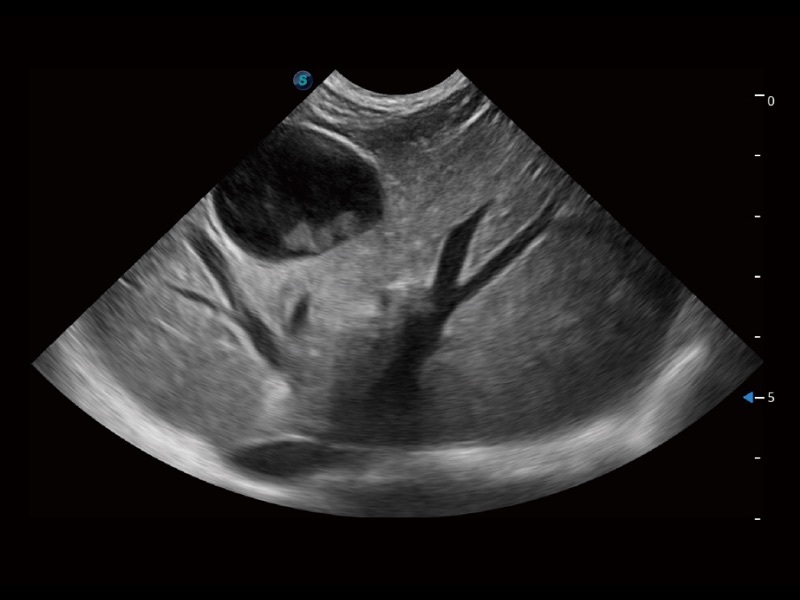

ProPet 70 进一步提升了微米成像算法,更加注重对基础原始图像的还原和保留,在有效减少斑点噪声、增强组织边界显示的同时,避免过度优化丟失真实的解剖信息。